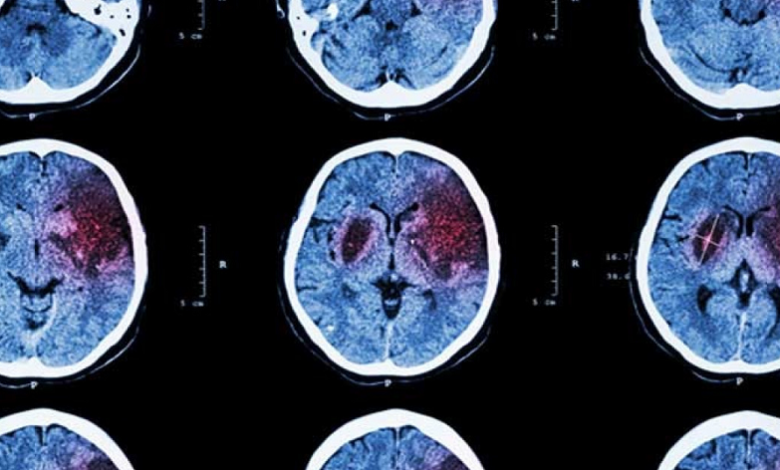

El accidente cerebrovascular, comúnmente conocido como derrame cerebral, es una emergencia médica que ocurre cuando se interrumpe el flujo sanguíneo al cerebro. Cada segundo cuenta, ya que la falta de oxígeno destruye millones de neuronas rápidamente.

Una cefalea explosiva, descrita como el peor dolor de la vida, puede indicar una hemorragia cerebral interna. Este síntoma aparece de forma súbita y suele acompañarse de náuseas, rigidez en el cuello o una gran sensibilidad sensorial.